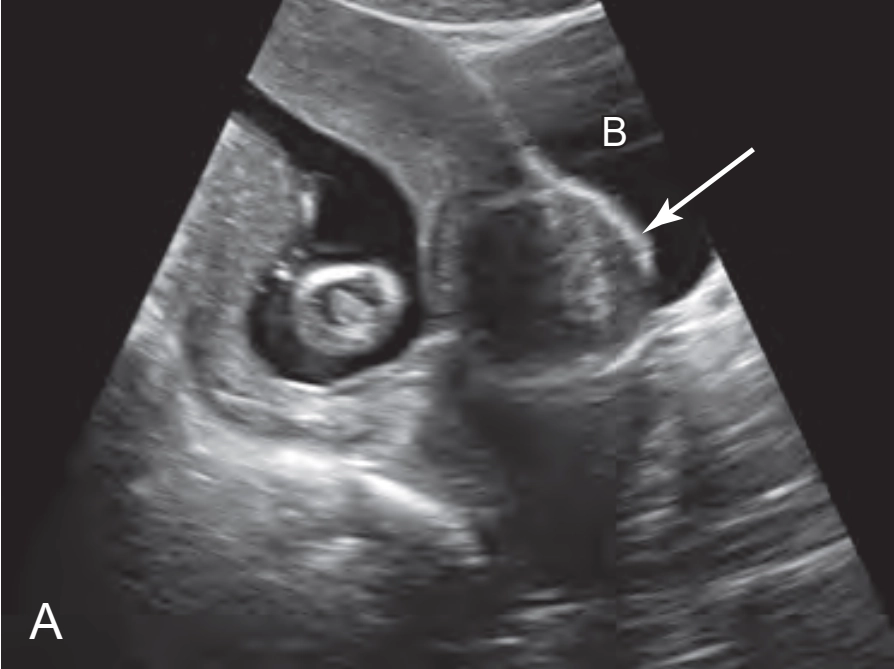

Khối phồng màng đệm (Chorionic Bump)

Nhân xơ trong thai kỳ (Fibroids)